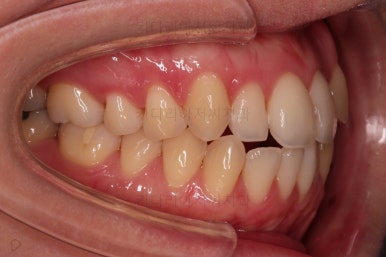

초진 시, 입안의 모습입니다.

좌측 송곳니가 덧니처럼 튀어나가 있고, 송곳니 옆의 작은 억므니가 안으로 쏙 들어가서 덧니 느낌이 더 강조되어 보이네요.

위아래 앞니가 긴밀하게 겹침이 없는 약간의 개방교합(오픈바이트, Openbite) 경향이 보입니다.

웃거나 말할 때 드러나는 치열이 삐뚤어서 심미적으로 좋지 못하고요.